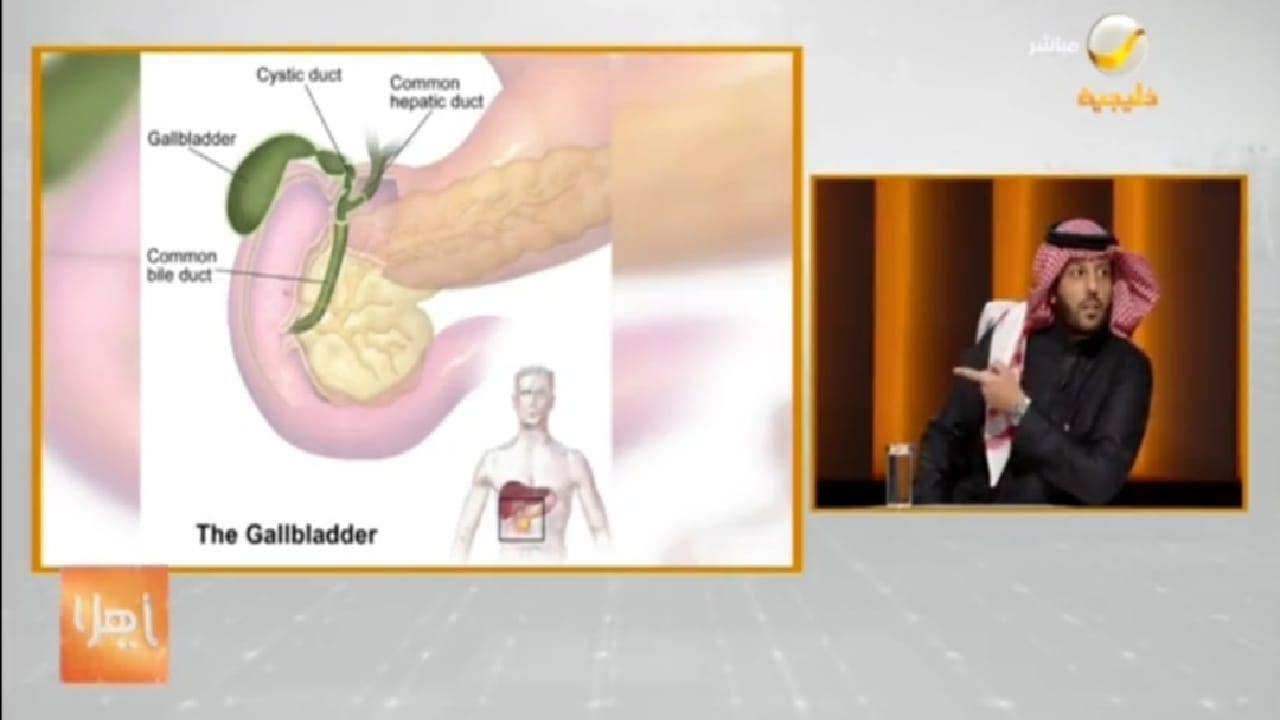

استشاري : الجراحة هي الحل الأمثل لحصوات المرارة (فيديو)

منذ 3 سنة

0

1407